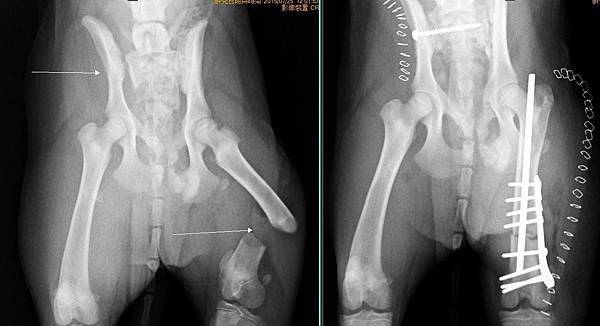

大腿開放性骨折、骨盆脫臼

麗卡被車子壓到

導致大腿開放性骨折、骨盆脫臼

經過醫療團隊努力後

一一修復

很快的在一周內恢復行走能力